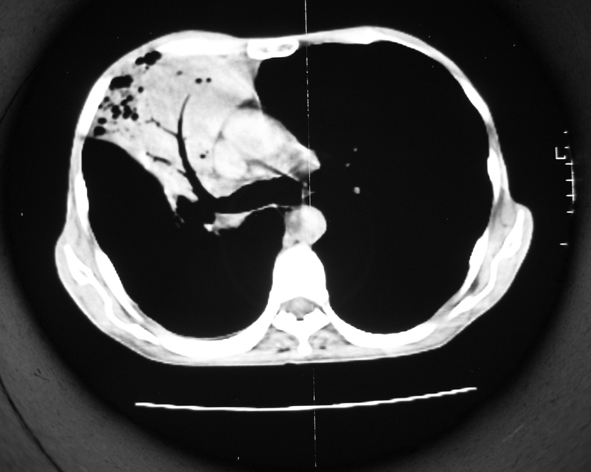

男53岁,咳嗽气短,以往身体健康.

右肺上叶多发多形态空洞及增殖灶,可见团块钙化,胸膜肥厚、粘连,考虑继发型肺结核可能性大

1.右肺上叶干酪性肺炎,2。肺气肿,肺大泡

右肺上中叶结核干酪性肺炎

右肺中上叶干酪性肺炎。